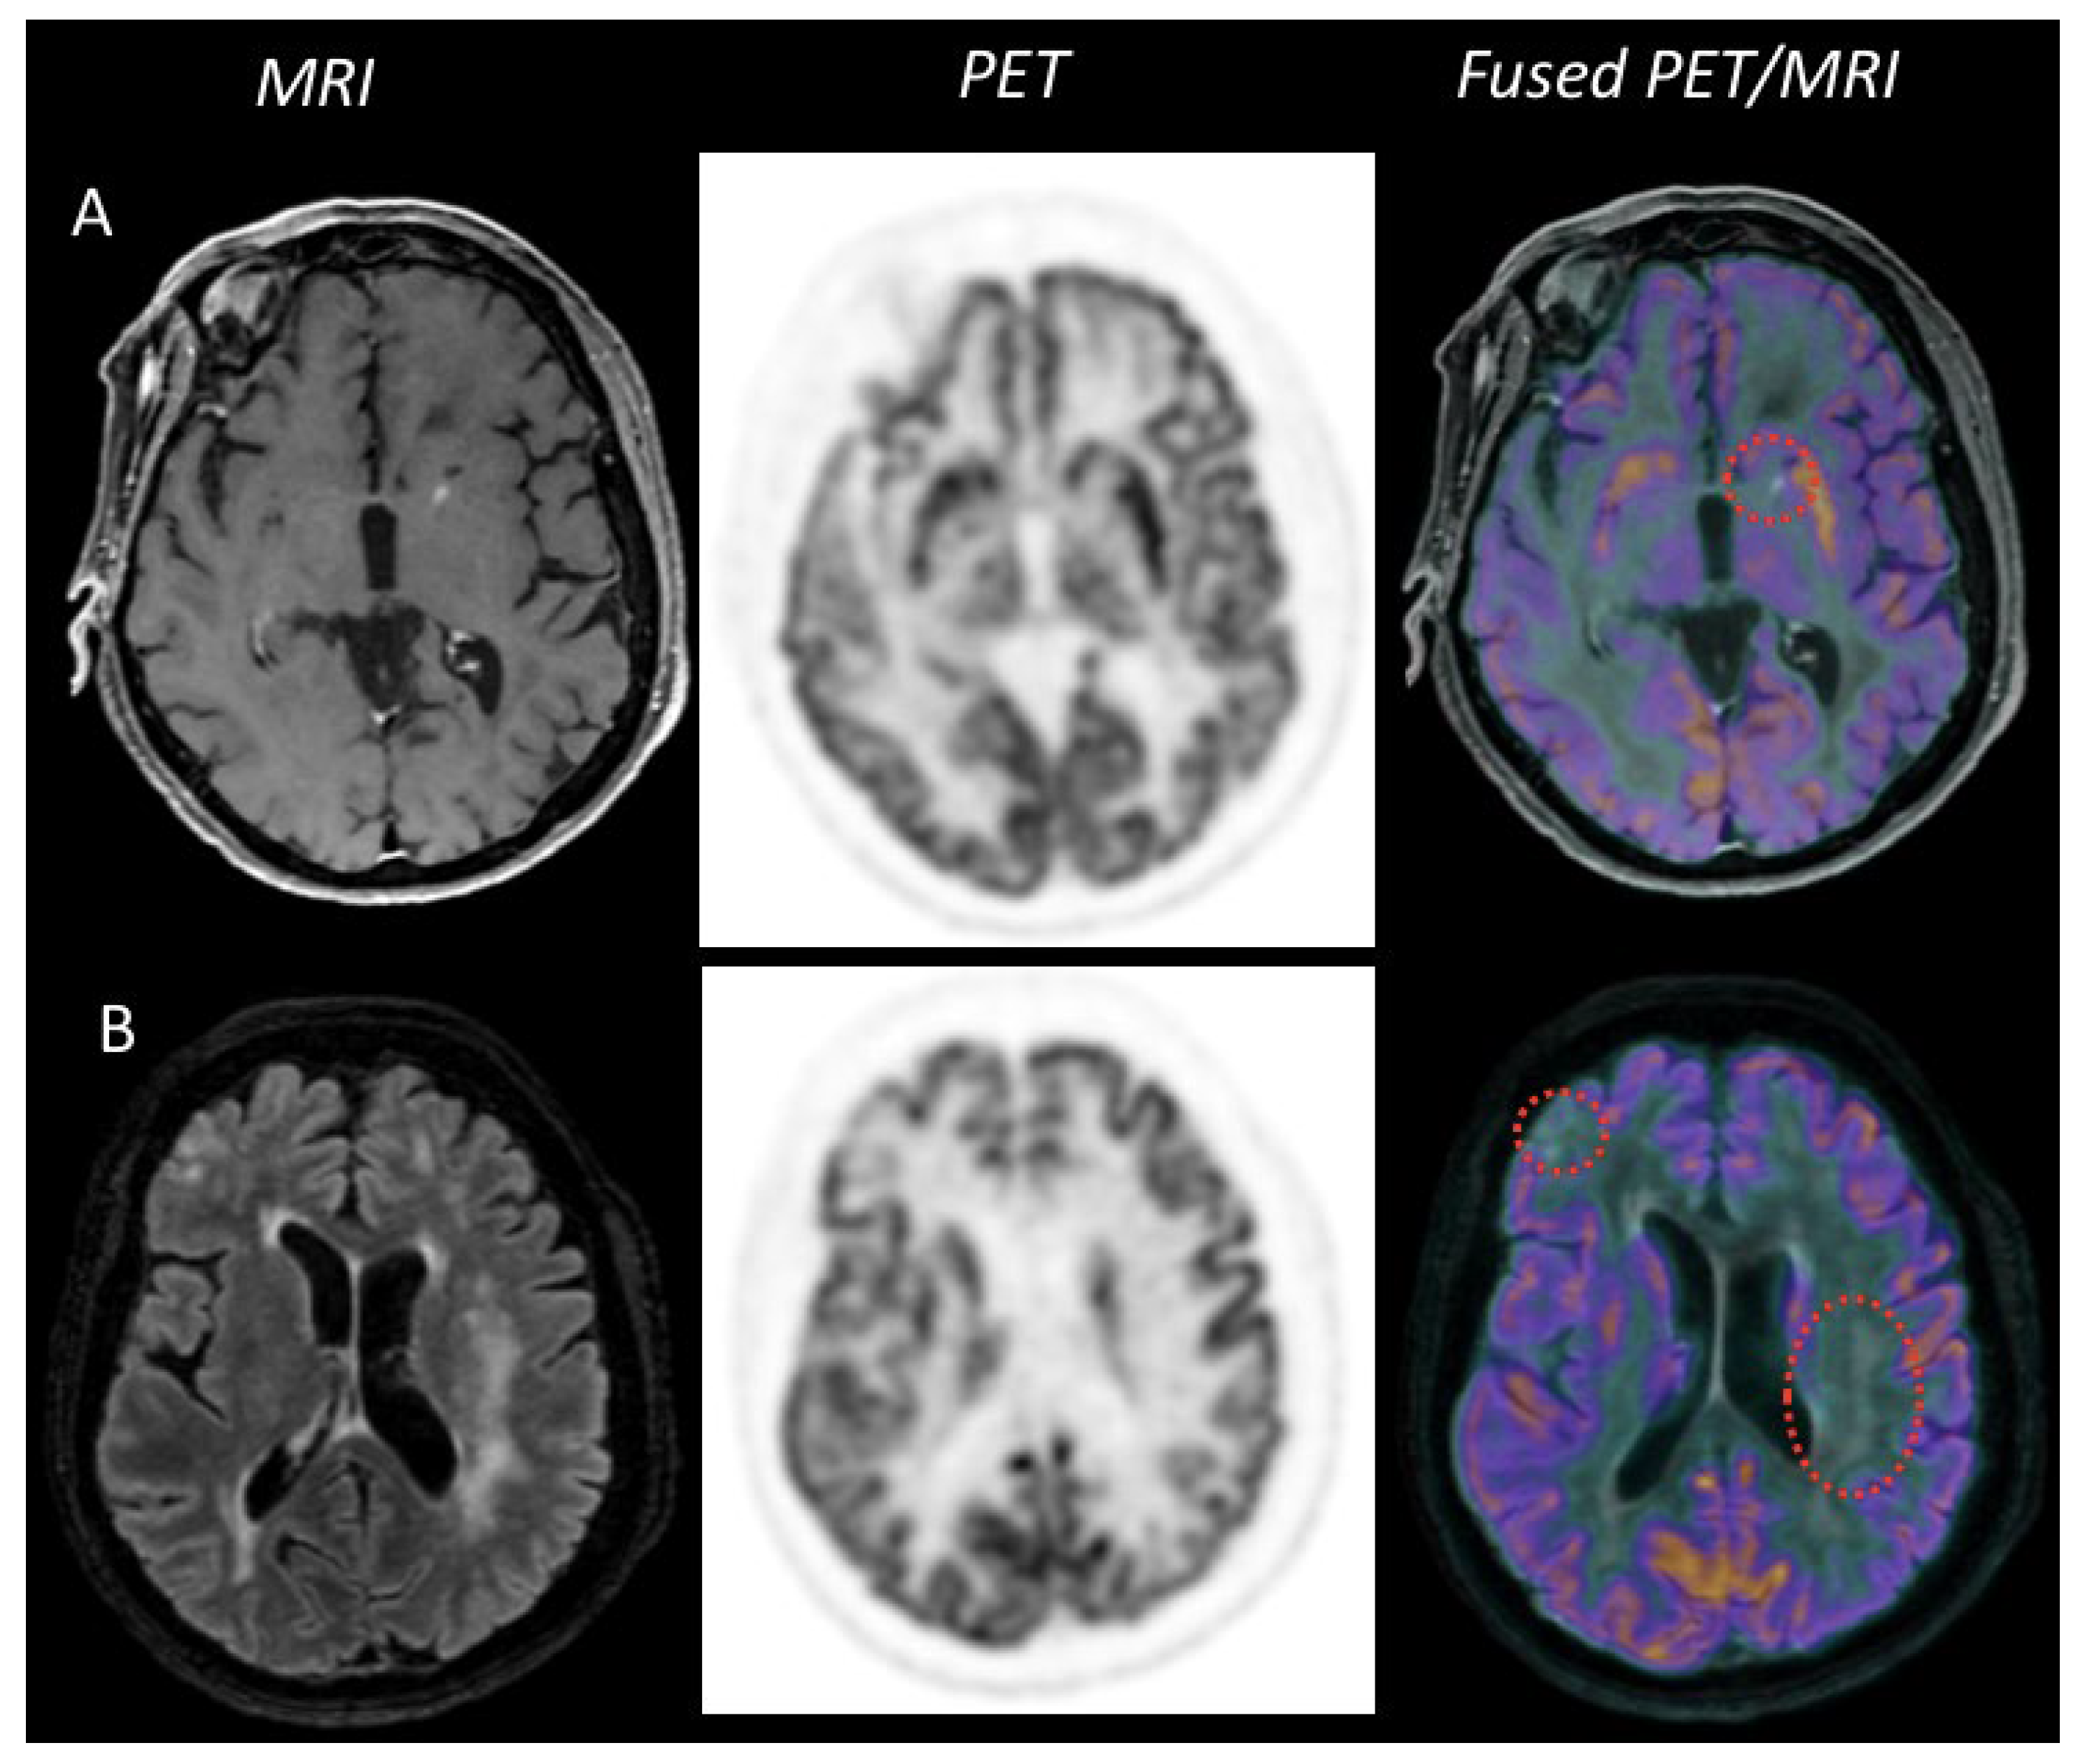

2.2. 18F-FDG Positron Emission Tomography (PET)

2.2.1. Features at Diagnosis